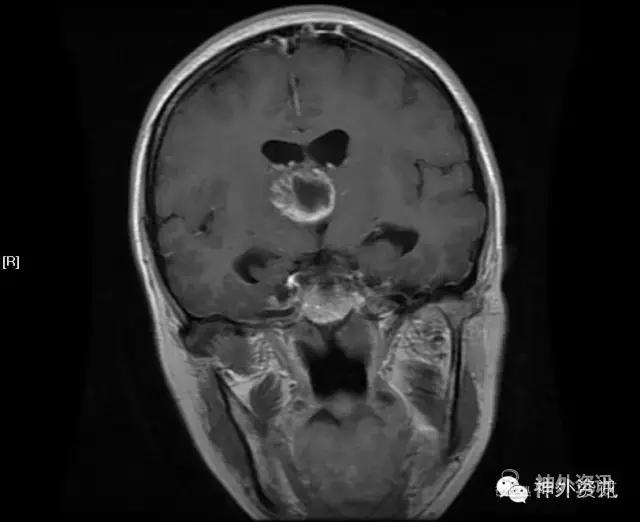

MRI:右侧丘脑占位,考虑胶质瘤可能性大(Ⅲ-Ⅳ级),病灶累及中脑右侧大脑脚,轻度脑积水;不除外转移瘤可能,请结合相关病史及检查。

影像学检查: